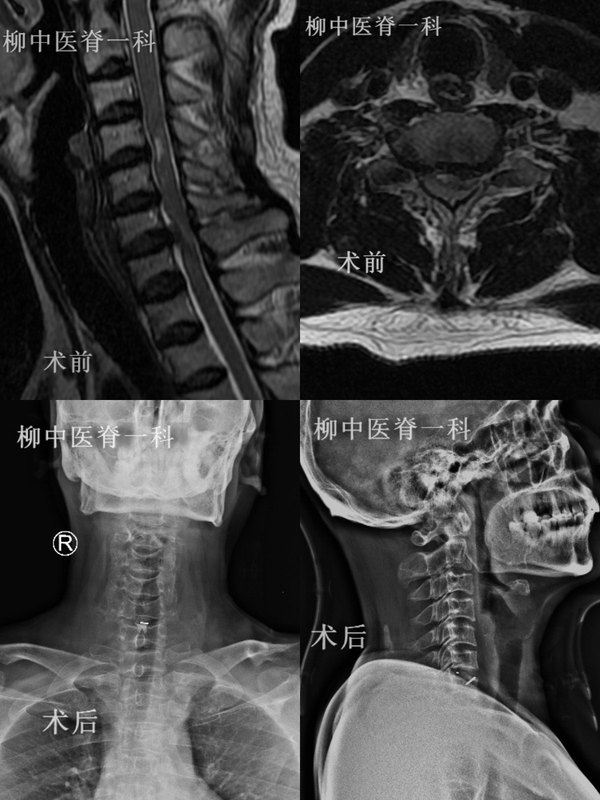

顯微鏡技術(shù)引領(lǐng)脊柱外科進(jìn)入精準(zhǔn)時(shí)代48歲的出租車司機(jī)謝師傅,平時(shí)就患有頸椎病,由于疲勞導(dǎo)致了頸肩痛加重,經(jīng)過推拿治療不僅無效反而加重,并逐漸出現(xiàn)了四肢麻木無力、行走不穩(wěn)、小便失禁等癥狀,經(jīng)人介紹找到柳州市中醫(yī)醫(yī)院脊柱一科的黃承軍主任,經(jīng)過詳細(xì)的檢查,綜合磁共振等影像表現(xiàn),診斷為“頸椎間盤突出癥”,建議手術(shù)治療。經(jīng)過充分的準(zhǔn)備,黃主任帶領(lǐng)的手術(shù)團(tuán)隊(duì)為謝師傅進(jìn)行了“顯微鏡下前路頸椎間盤切除,零切跡融合器植入術(shù)”,通過僅僅3厘米的微小切口就完成了手術(shù),術(shù)后第二天患者癥狀明顯緩解,5天后出院,1個(gè)月后完全康復(fù)恢復(fù)了工作。 37歲的何女士10年前做過“腰椎間盤摘除術(shù)”,因?yàn)橐淮尾簧髋麖?fù)發(fā)了,保守治療兩個(gè)多月無任何效果,看了很多專家都建議手術(shù)。以往這樣的翻修手術(shù)技術(shù)復(fù)雜、創(chuàng)傷大、出血多、恢復(fù)慢,而且容易損傷神經(jīng),給患者帶來巨大的心理壓力。后來慕名找到黃承軍主任,經(jīng)過精心設(shè)計(jì)和準(zhǔn)備,黃主任為她做了“顯微鏡下椎間盤切除,椎間融合,單側(cè)椎弓根螺釘固定術(shù)”,手術(shù)切口僅3.5厘米,出血還不到30毫升,術(shù)后第二天就能起床活動(dòng),兩周后就回單位上班了。 脊柱顯微外科是傳統(tǒng)脊柱外科技術(shù)與顯微外科技術(shù)的完美結(jié)合,除具有切口小、創(chuàng)傷小、出血少和術(shù)后恢復(fù)快等優(yōu)點(diǎn)外,手術(shù)視野照明充分、清晰度高,而且放大數(shù)十倍,手術(shù)醫(yī)生對(duì)于解剖結(jié)構(gòu)看得非常清楚,手術(shù)也因此可以更加安全而精細(xì)。上世紀(jì)80年代以來,脊柱顯微外科技術(shù)在發(fā)達(dá)國家蓬勃發(fā)展, 已成為治療脊柱退行性疾病的金標(biāo)準(zhǔn)技術(shù)。然而由于種種原因,我國脊柱顯微外科技術(shù)的發(fā)展嚴(yán)重滯后。 在傳統(tǒng)的脊柱手術(shù)中,醫(yī)生是通過裸眼手術(shù)。然而人的裸眼視力是有限的。舉例而言,再優(yōu)秀的射手,使用普通步槍裸眼瞄準(zhǔn),要想在500米距離上準(zhǔn)確命中目標(biāo)幾乎是不可能的,而裝備了高倍率瞄準(zhǔn)鏡的狙擊手卻可以創(chuàng)造3000米以上超遠(yuǎn)距離一槍斃命的奇跡。顯微鏡就是脊柱外科醫(yī)生手中的高倍率瞄準(zhǔn)鏡,有了這個(gè)利器,脊柱外科手術(shù)才真正進(jìn)入了“精準(zhǔn)時(shí)代”。在顯微鏡的輔助下,我們一定能攻克更多的脊柱疾病!